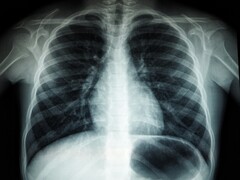

De onderzoekers melden dat slechts één kapperssessie van 10-20 minuten kan leiden tot de inademing van meer dan 10 miljard nanodeeltjes. Ze zeggen dat dit vervuilingsniveau vergelijkbaar is met wat u midden in het drukke verkeer op de snelweg krijgt. Gezien de grootte van deze deeltjes kunnen ze gemakkelijk diep in de longen doordringen. Dit kan leiden tot gezondheidsproblemen zoals ademhalingsstress, longontsteking en cognitieve achteruitgang.